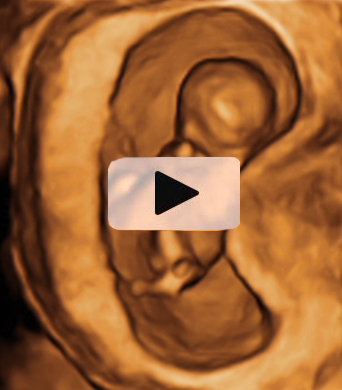

Ecografía semana 12: Bebé hacidendo movimientos vigorosos

He aquí un signo inequívoco de bienestar fetal: los movimientos vigorosos de un bebé en su semana 12 de gestación. La ecografía 4D muestra al niño en movimiento, junto con la placenta y el cordón umbilical dentro de la cavidad uterina.

Ecografía en 4D de feto de 12 semanas en movimiento

La variedad de movimientos de este bebé de 12 semanas de gestación es muy amplia. Las imágenes muestran cómo cambia de postura varias veces y agita con energía brazos y piernas. Para los ginecólogos, los movimientos de la criatura indican vitalidad, son un signo positivo de salud fetal. En la ecografía en 4D (vídeo) se aprecian casi todas las estructuras externas de la criatura, además del cordón umbilical y la placenta (ambos conectados entre sí), en el margen superior izquierdo de la cavidad uterina.